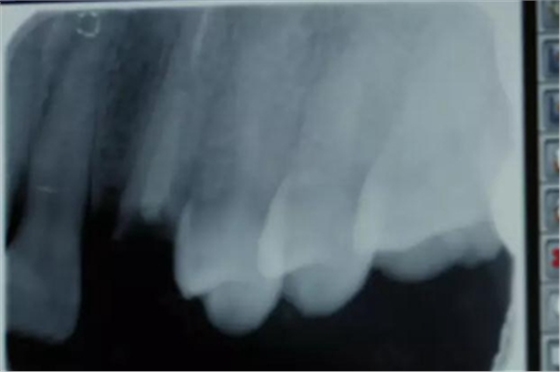

病例一 女性,20歲,大學(xué)生,要求補牙,檢查口內(nèi)可見A6大面積缺損,近中牙齦息肉,拍X片,根管充填物略差,但根周未見明顯陰影,口內(nèi)檢查無叩痛。建議患者冠延長手術(shù)+高嵌體修復(fù)。

患牙遠(yuǎn)中邊緣嵴完整,強度沒有降低,故擬保留遠(yuǎn)中邊緣嵴,高嵌體修復(fù)。首先去除腐質(zhì)及原墊底材料,流體樹脂+3M Z350XT樹脂墊底。局麻下行冠延長手術(shù)。在此需要提及個人的一個觀點。冠延長手術(shù)原則上要求3-6個月以上才能永久修復(fù)。但是個人喜歡后牙肩臺建立在齦上,所以修復(fù)后的修復(fù)體邊緣位于牙齦上方1mm,對牙周的愈合影響較小(如果為齦下邊緣則要慎重),故該患者術(shù)中按照齦上邊緣的設(shè)計進行冠延長手術(shù)。以下為術(shù)中: